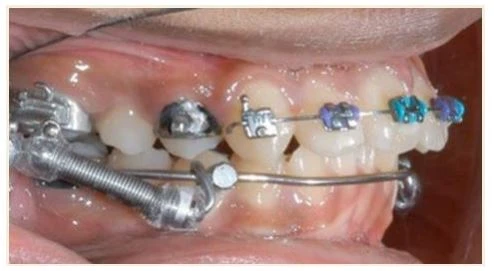

Sau khi đã có chẩn đoán và bệnh án ở lần tư vấn thứ hai, đây là lúc đặt khí cụ gắn chặt. Trong hầu hết các ca, nên đặt khâu lên một số răng cối, đặc biệt là các răng sau nhất của cung hàm, sau đó gắn mắc cài từ 4-4 hoặc 5-5. Dán mắc cài thì không cần phải tách khe trước nhưng nếu đặt khâu vào răng thì cần phải tách khe.

Nha sĩ cần xác định kích thước khâu trực tiếp trên bệnh nhân, hoặc bạn hãy đo kích cỡ khâu trên mẫu hàm nghiên cứu. Khâu có thể là khâu trơn hoặc có hàn thêm vật gắn phụ mặt lưỡi hoặc má theo lựa chọn của nha sĩ. Có rất nhiều loại móc hàn khác nhau cả mặt trong và mặt ngoài để áp dụng trên từng bệnh nhân khi chỉ định khác nhau, loại bỏ hệ thống cồng kềnh các loại khâu hàn trước và dây cung thẳng kèm theo. Khâu hàn trước được sử dụng ở Mỹ từ năm 1962. Trước đó, nha sĩ hàn mỗi móc phụ vào khâu trong miệng bằng việc “bấm” khâu và hàn thêm vào. Quá trình này rất mất thời gian, nhưng cho phép nha sĩ chọn được khí cụ cá nhân hóa phù hợp cho mỗi bệnh nhân.

Toàn bộ khâu răng cối đều có ống mặt ngoài có thể mở nắp. Khe dây cung được phủ bằng một nắp dạng bản để tạo thành ống. Vì có ống răng cối ở răng cuối cùng nên bạn không cần phải buộc dây (bằng dây thép hoặc chun) vào răng này. Bản nắp này có thể lấy khỏi khâu bằng dụng cụ mở nắp khâu chuyên dụng để trở thành một mắc cài tiêu chuẩn có khe.

Động tác này thực hiện khi bạn muốn tạo điểm bẻ trên dây cung giữa răng 6 và răng 7. Ống mặt ngoài được hàn vào răng 7 không bật nắp được, chỉ là một ống đơn thuần, trừ phi có yêu cầu đặc biệt (sử dụng ống răng 6 trên răng 7 cũng được nếu khâu cả răng 8). Khâu cũng có móc ở mặt ngoài gần để móc chun, lò xo hoặc chun chuỗi.

Hầu hết các trường hợp đều gắn khâu răng 6. Lực cắn sẽ gây ra bong các mắc cài trên hầu hết bệnh nhân trừ những người cực kì cẩn thận. Nếu sử dụng headgear, TPA, LLA thì yêu cầu răng 6 đó phải được gắn khâu chứ không dán. Răng gắn khâu sẽ chịu được lực mạnh hơn từ khí cụ. Nếu mắc cài bị bong tại cuối dây cung, thì bệnh nhân lại cần một lần gặp khẩn cấp để sửa lại phần dây cung bị lộ ra. Gắn khâu bảo vệ sẽ giảm được các rắc rối này.

2.6. Chuyển dạng khâu thành mắc cài

Chuyển ống răng 6 thành mắc cài khi gắn khâu ở cả răng 6 và răng 7. Khi biến ống thành mắc cài trên khâu răng 6, rất dễ gắn dây cung cứng, dễ bẻ dây giữa các răng 6-7, và đặt lò xo mở để di xa răng cối.

Ống răng 6 có thể chuyển dạng thành mắc cài bằng dụng cụ chuyển dạng. Lấy bỏ bản ngoài của ống bằng động tác “mở hộp” trên dụng cụ. Mắc cài sẽ cần được buộc như đối với mắc cài thông thường.

Dụng cụ chuyển dạng mắc cài được dùng để lấy bỏ bản ngoài, chuyển “ống” thành “mắc cài”, sau đó cần phải buộc như mắc cài.